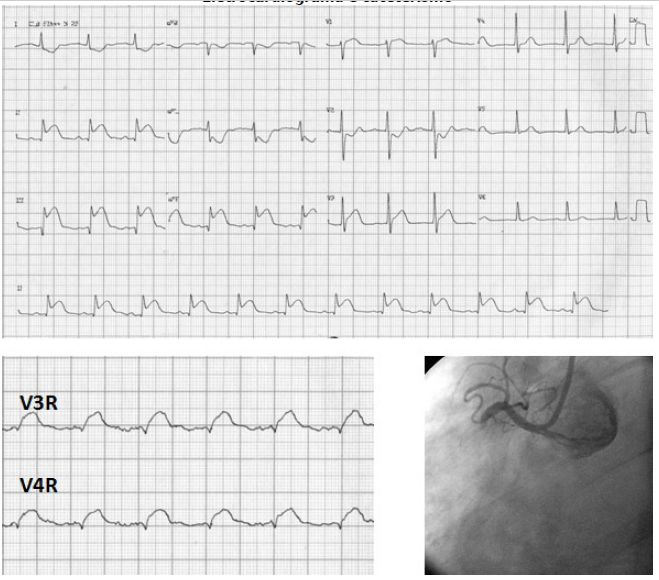

Paciente hipertensa e diabética deu entrada no ponto atendimento, apresentando dor torácica em aperto, associada a náuseas. No hospital, foi diagnosticado com síndrome coronariana aguda e levado ao cateterismo.

Eletrocardiograma e cateterismo

Em relação a paciente acima, qual droga deve ser evitadas nesse paciente: